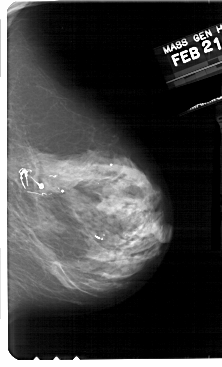

A_1930_1.RIGHT_CC

RIGHT_CC LINES 5131 PIXELS_PER_LINE 3151 BITS_PER_PIXEL 12 RESOLUTION 43.5 NON_OVERLAY